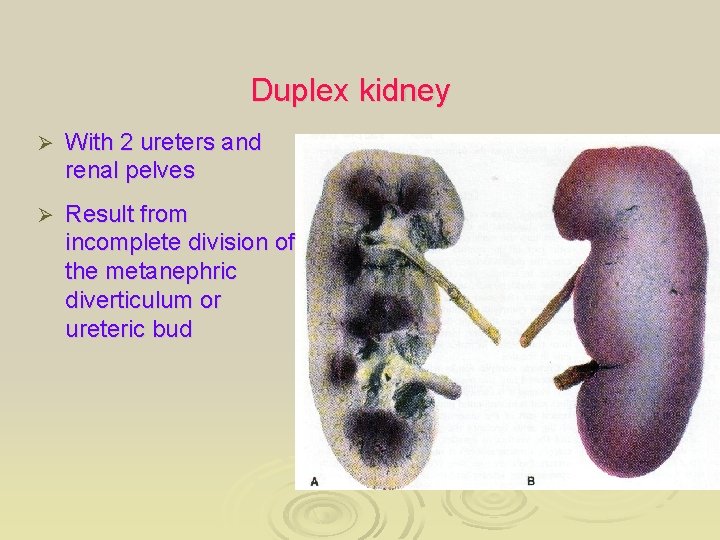

Duplex kidney Ø With 2 ureters and renal pelves Ø Result from incomplete division of the metanephric diverticulum or ureteric bud